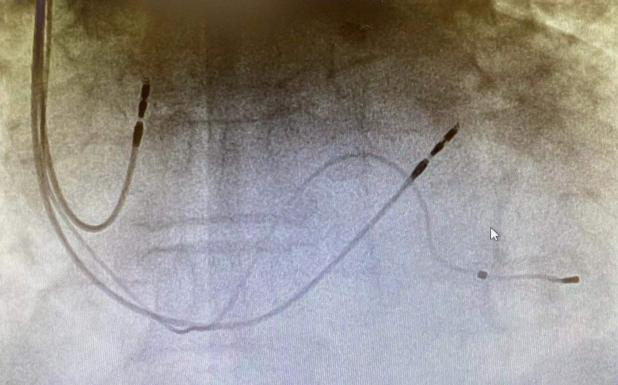

經(jīng)過前期充分準備,心內科汾東二病區(qū)專家為張大爺順利植入CRT,手術僅用時50分鐘。

術后,經(jīng)過精心護理,張大爺恢復良好,起搏器起搏與感知良好,復查心電圖QRS由術前204ms縮短至116ms,已于8月2日康復出院。